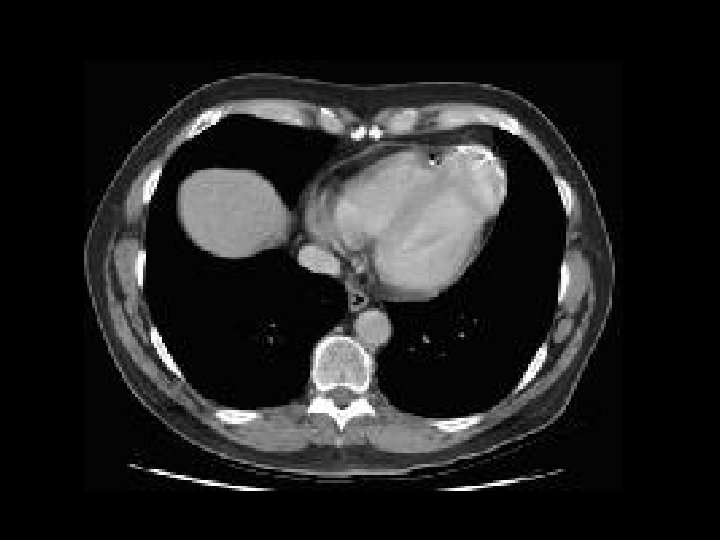

Clínica y diagnóstico o Métodos de diagnóstico por imágenes n Ventriculografía izquierda n Ecocardiografía n TAC n Resonancia magnética

Clasificación o Tres categorías clínico-patológicas: n Aguda n Subaguda n Crónica con formación de un falso aneurisma.

Características del falso aneurisma 1. 2. 3. 4. La pared del falso aneurisma no contiene células miocárdicas. Usualmente de localización posterior. Usualmente tienen un cuello estrecho. Propensos a ruptura